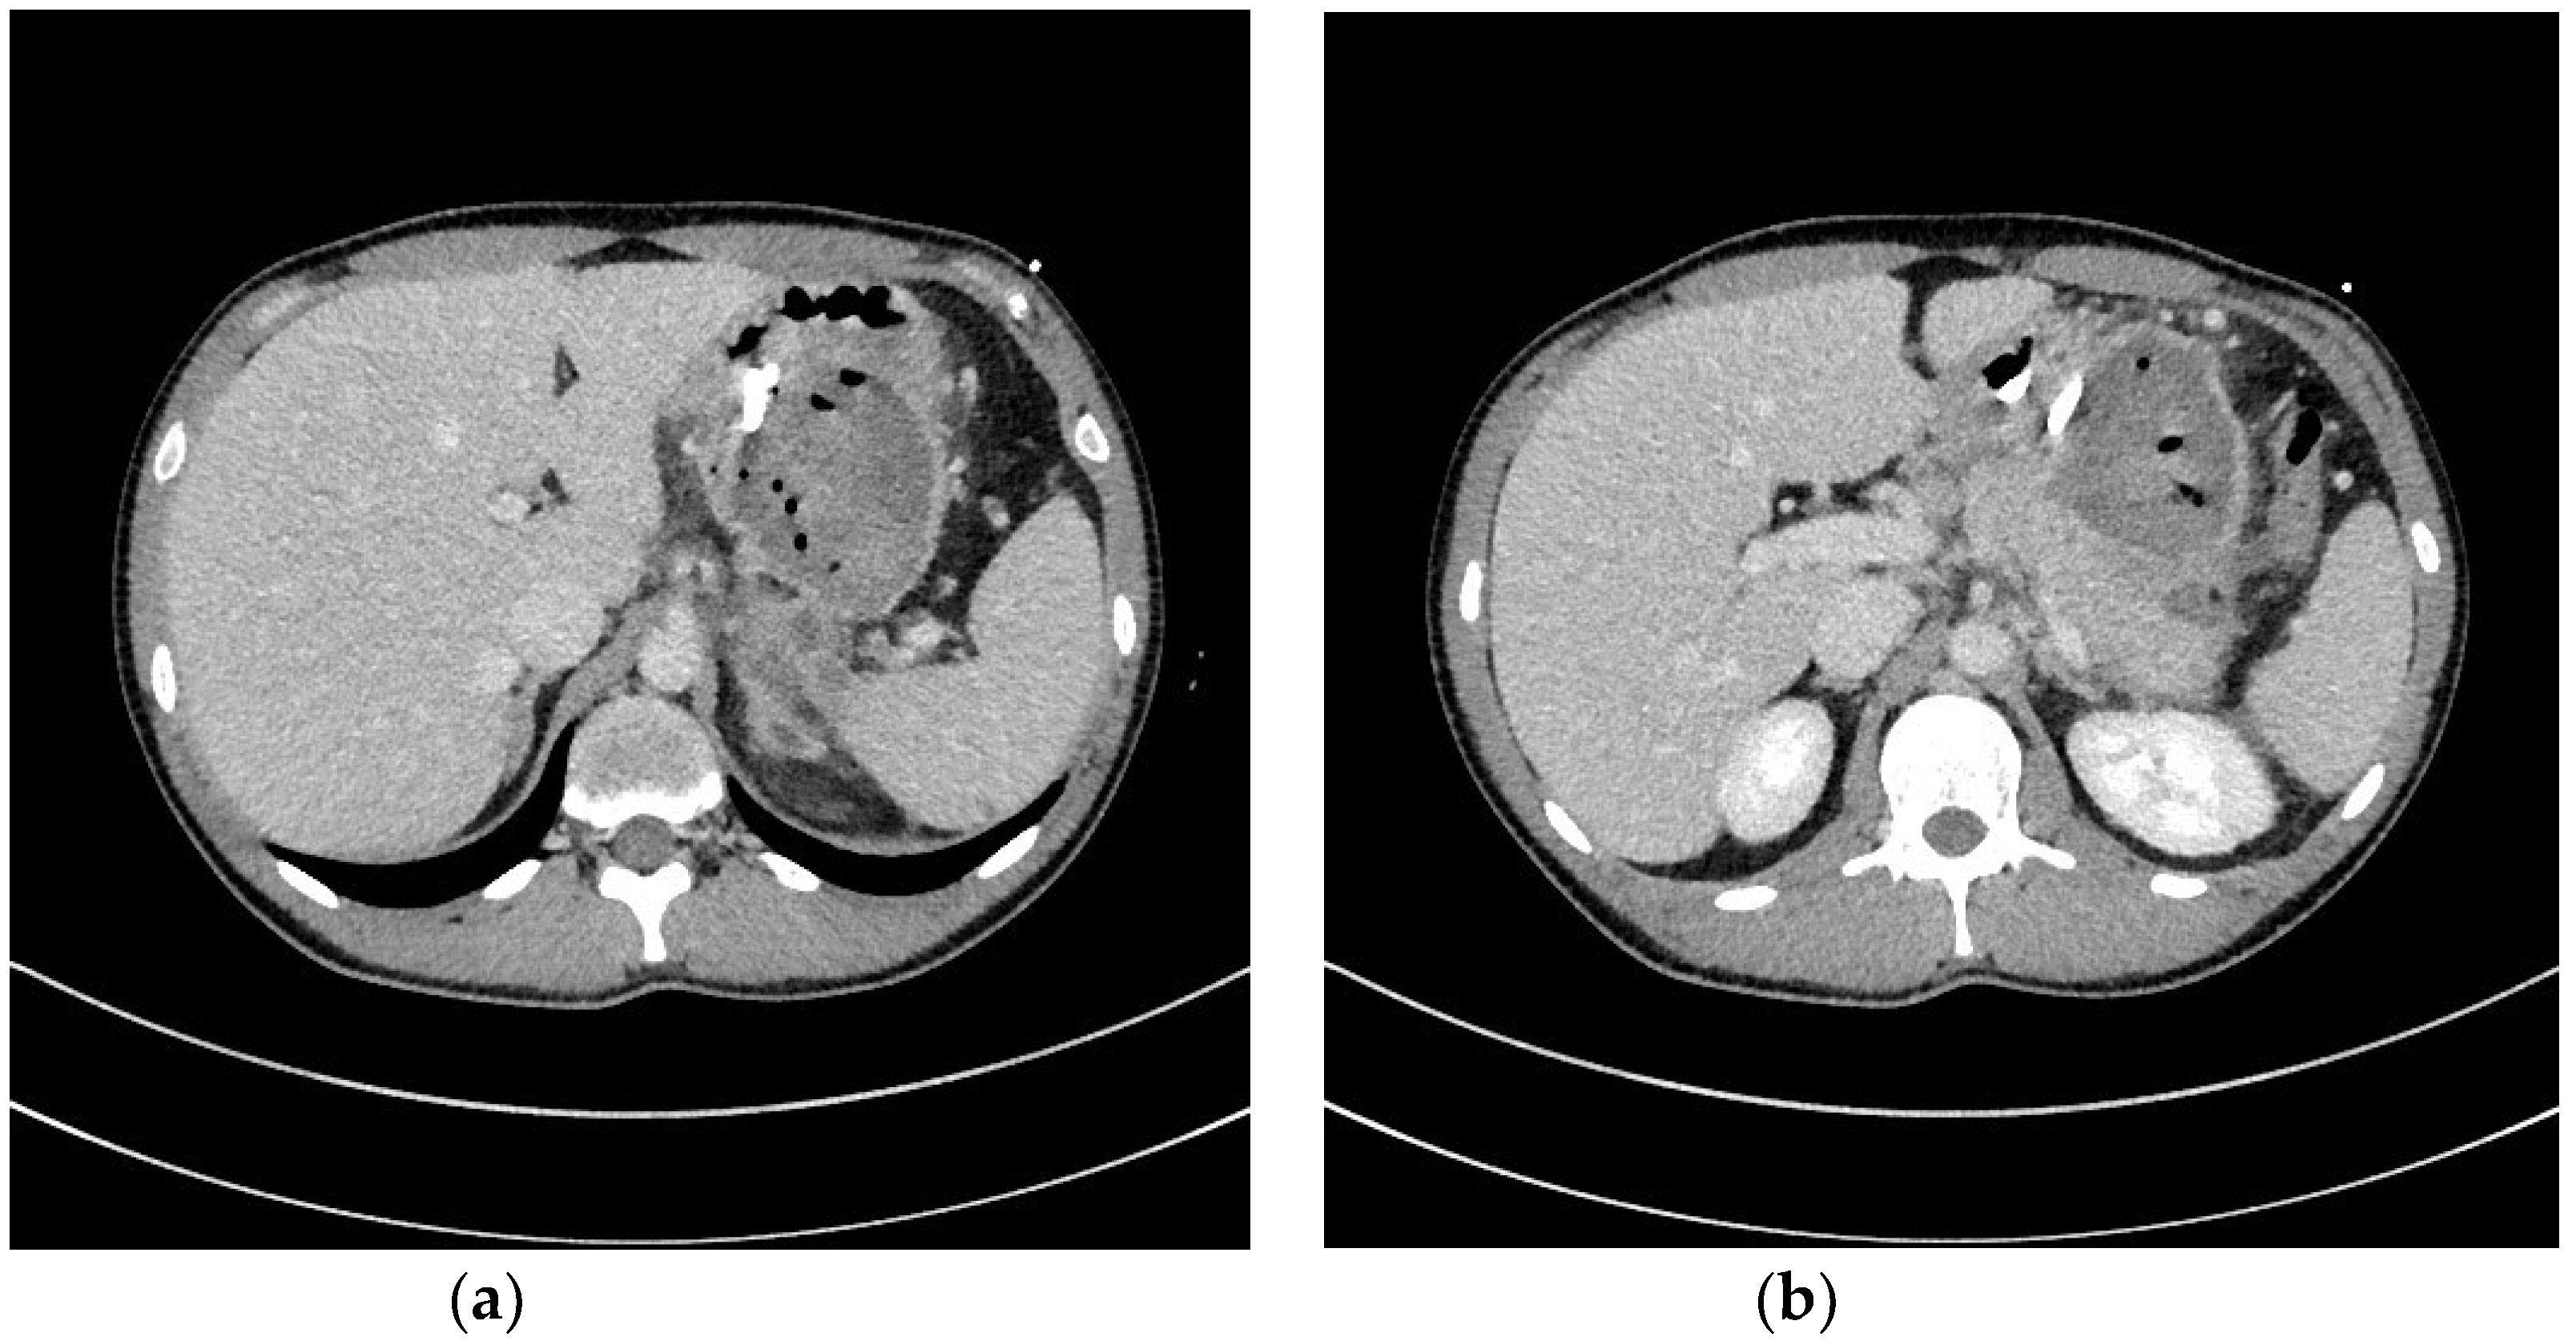

| Transmural endoscopic drainage with use of SEMSs | Active (with nasal drain) or passive (without nasal drain) transmural drainage accomplished via insertion of metal stent (SEMS) through the transmural fistula into lumen of necrotic collection. Indications for this type of drainage are extensive WOPN containing poorly-liquefied necrotic tissues, in which endoscopic necrosectomy may be necessary in the next step. SEMSs are usually used in the endoscopic treatment of WOPN up to sixth week from the beginning of ANP. |